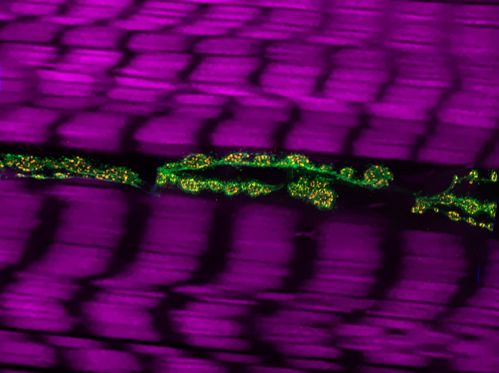

Uno studio del Cnr identifica nel controllo dei livelli della proteina spastina un elemento chiave per recuperare la degenerazione neuronale associata alla patologia